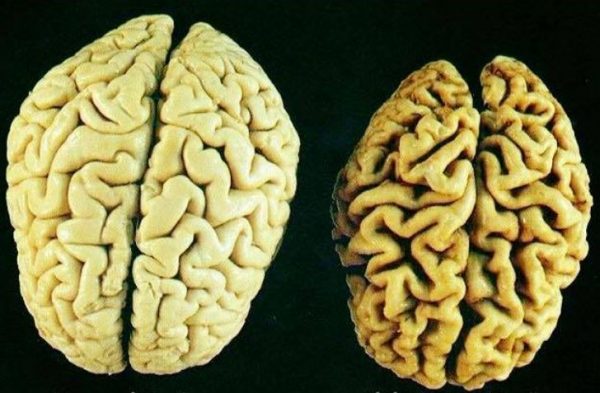

Οι ασθενείς με σημαντική εγκεφαλική ατροφία (Εικόνα 3) διατρέχουν υψηλότερο κίνδυνο για υποσκληρίδιο αιμάτωμα. Αυτή η κατηγορία περιλαμβάνει τους ηλικιωμένους, εκείνους με ιστορικό κατάχρησης αλκοόλ και αυτούς με προηγούμενη τραυματική εγκεφαλική βλάβη. Σε αυτούς τους ασθενείς ακόμα και ασήμαντο τραύμα στο κεφάλι μπορεί να προκαλέσει υποσκληρίδιο αιμάτωμα. Έτσι, το υποσκληρίδιο αιμάτωμα παρατηρείται συχνότερα σε ηλικιωμένους ασθενείς παρά σε νεότερους.